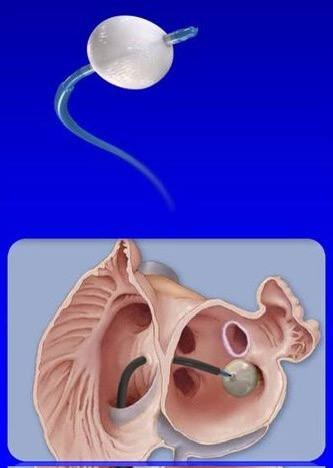

一次性使用球囊型冷冻消融导管

项目类型

器械质押区

起投金额

1200USDT

每日释放:0.75

释放周期:15 天

已购: 51666

剩余: 0